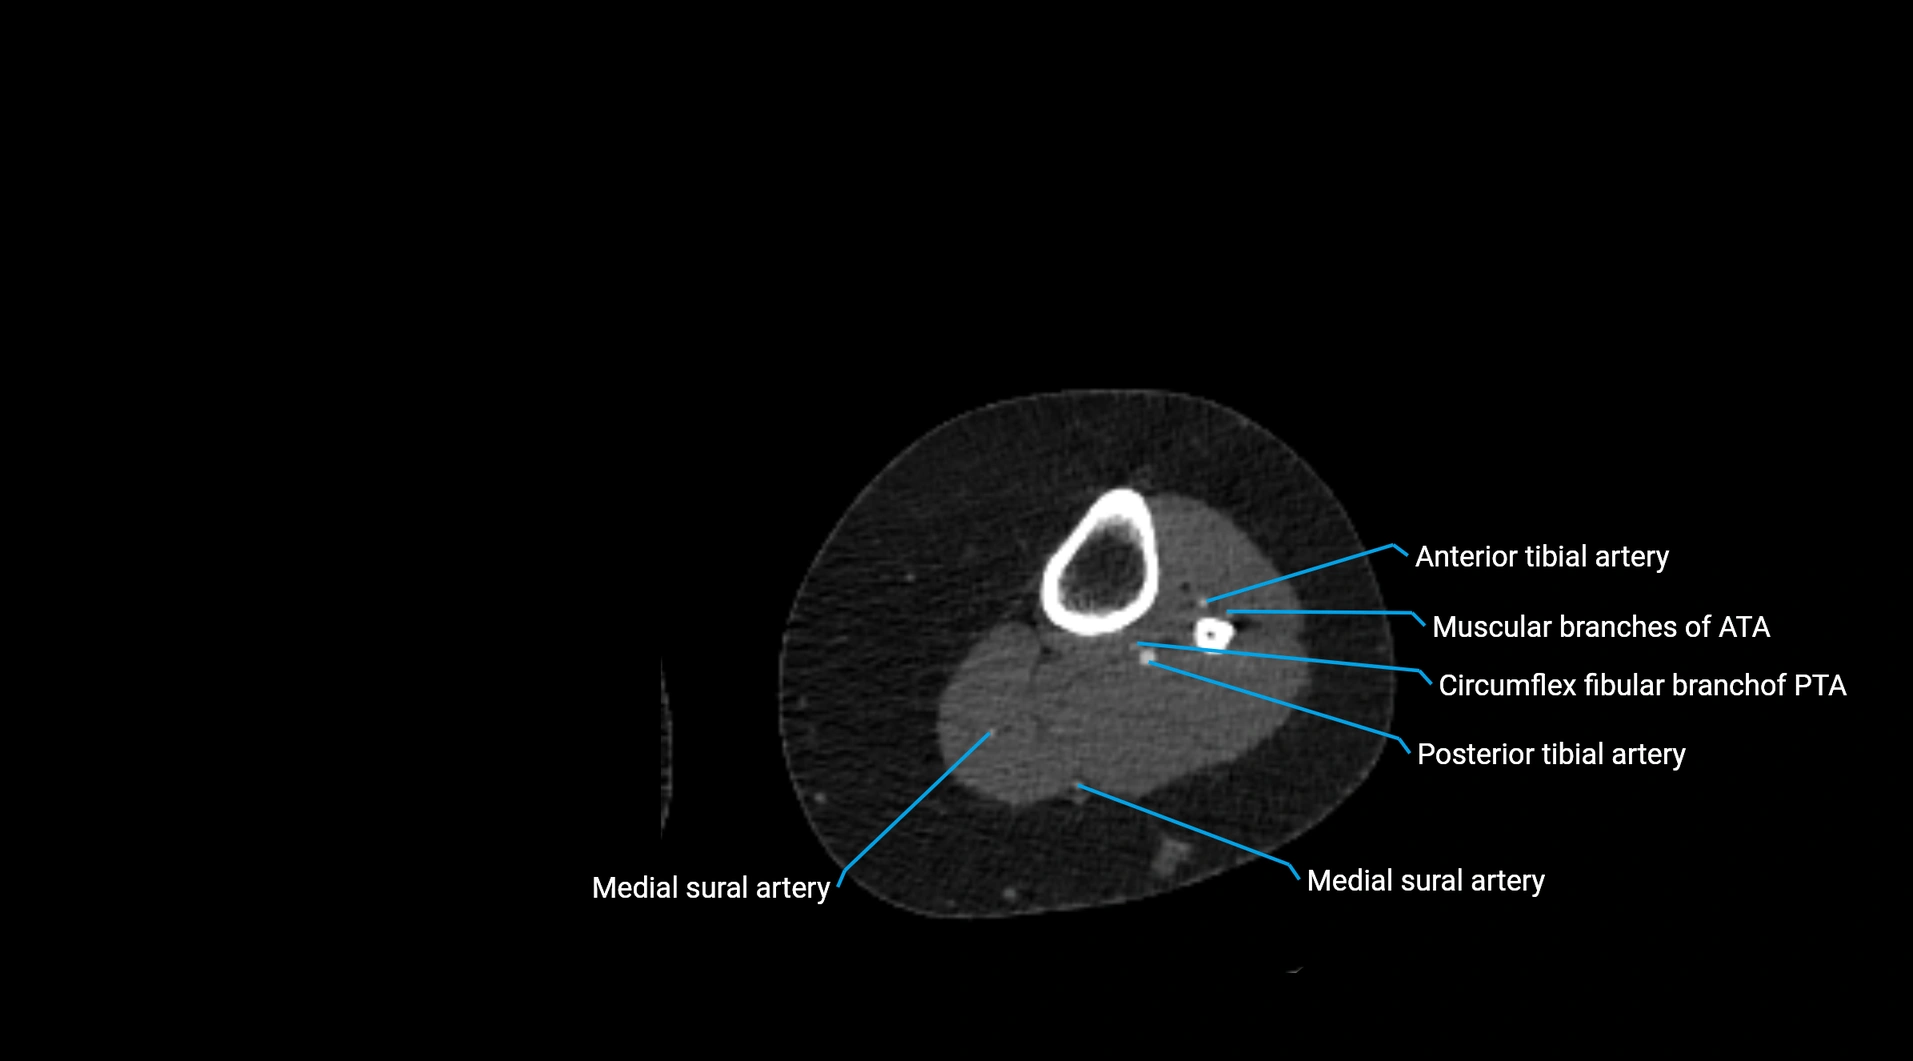

CT images

image